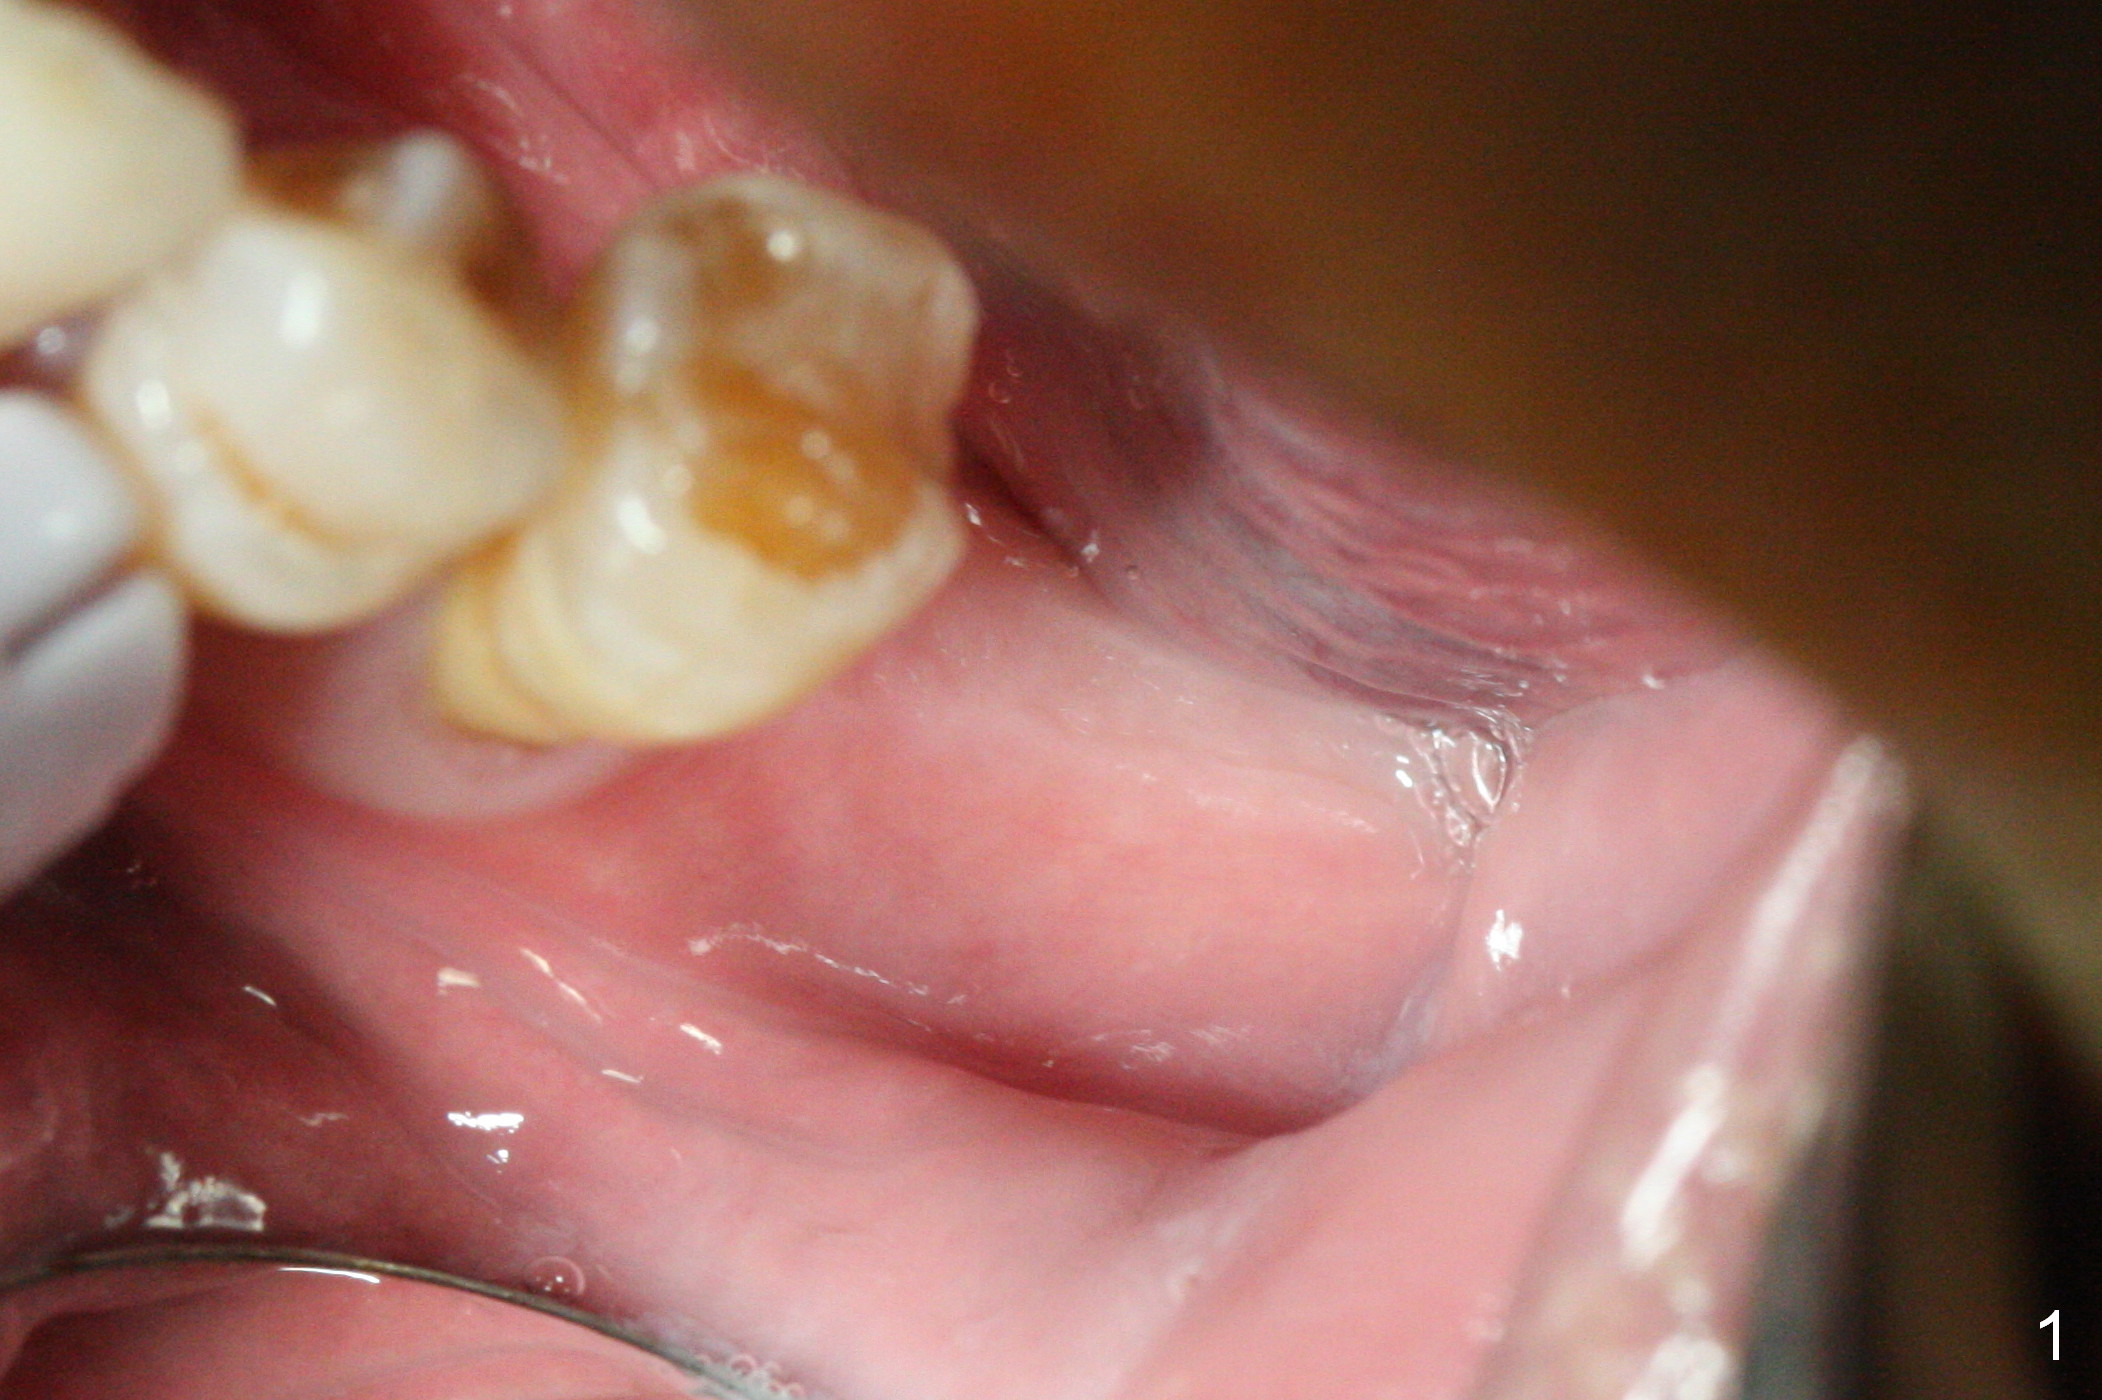

As indicated by CBCT, the ridge at the site of #19 is pointed (Fig.1). After regional ridge reduction (Fig.2) and use of 2 mm pilot drill for 8.5 mm, the depth is actually ~ 10 mm. After sequential osteotomy until 4.3x10 mm drill, the osteotomy is in fact 11.5 mm deep; a 5x11.5 mm implant is placed with <35 Ncm (Fig.3). Panoramic X-ray shows the implant close to the superior border of the Inferior Alveolar Canal (Fig.4 red dashed line). The ridge looks wider and more bulging (*) when a 6.5x5.5(5) mm abutment, allograft/Osteogen and Osteotape (GBR) are placed (Fig.5 (lingual) and 6 (buccal)). Periodontal dressing is then applied. There is no postop paresthesia. The abutment dislodges 3 weeks postop. A healing abutment is placed (6.5x4 mm). The patient returns for restoration 4 months postop; bone density appears to increase around the implant (Fig.7 arrowheads). When a 7.5x5(4) mm abutment is placed, there is transient pressure on the gingiva (blanching). The mesial gingival trough is formed by Diode laser prior to impression.